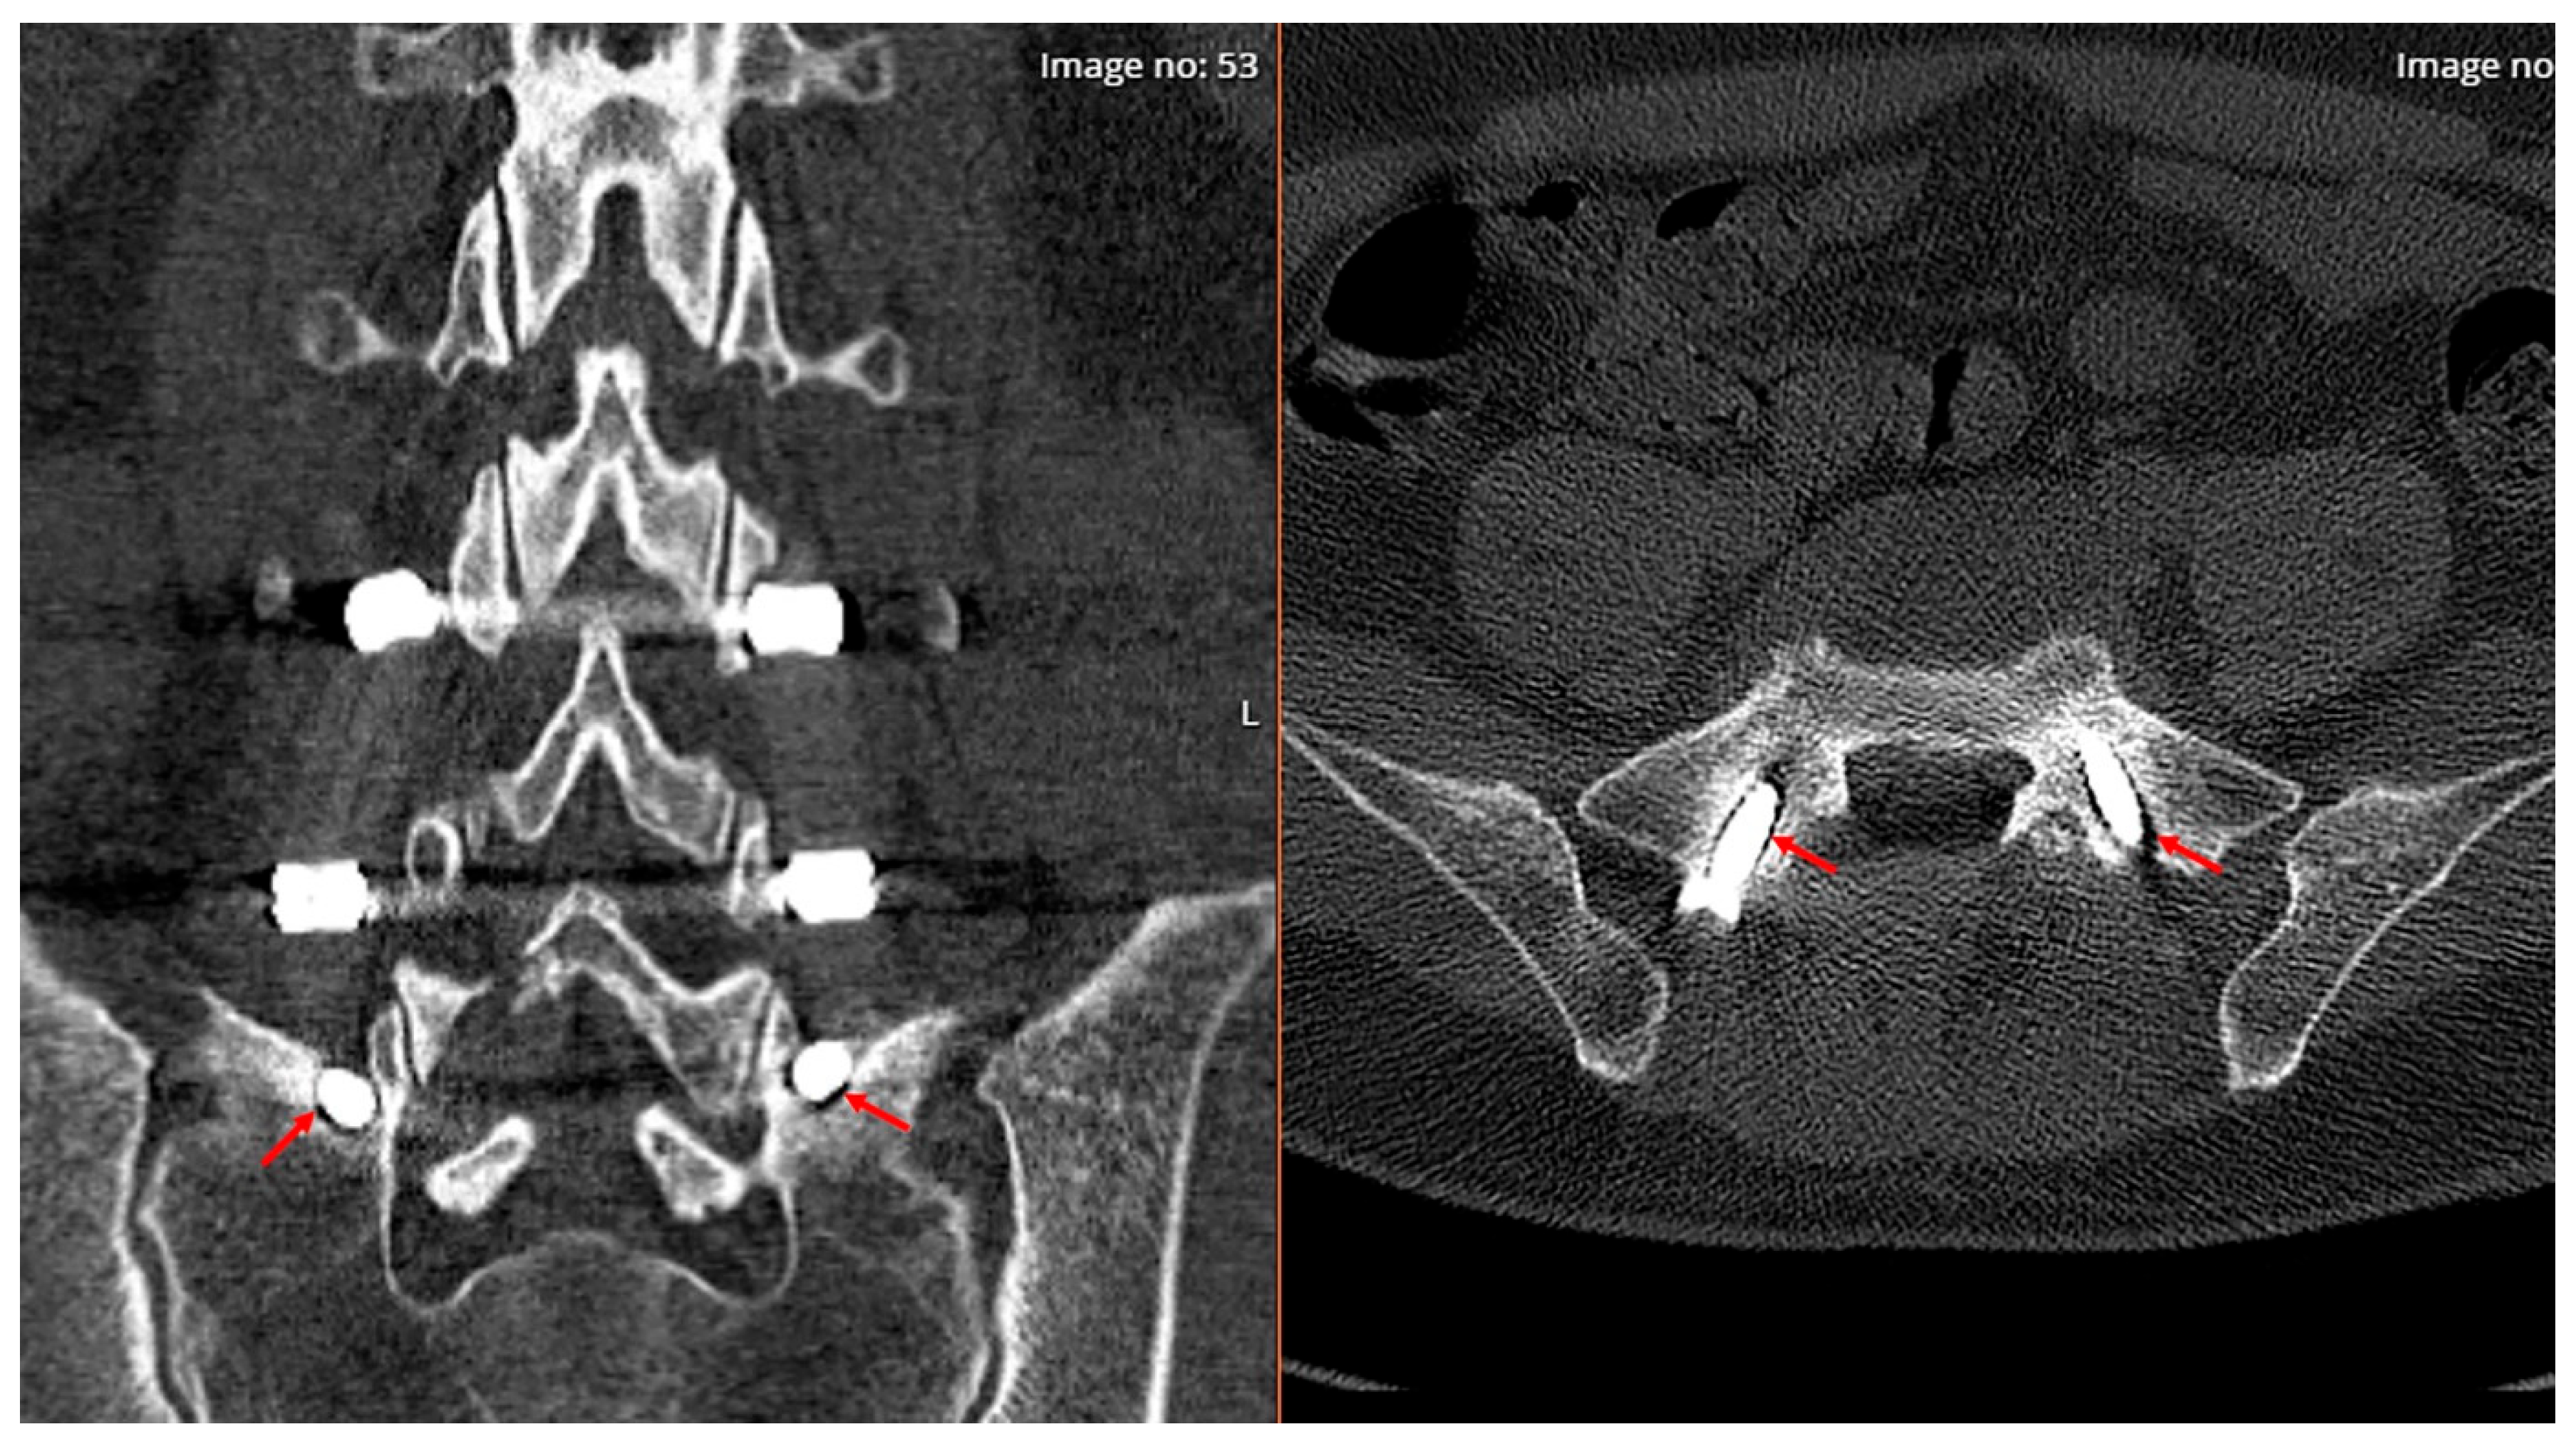

2.3. Radiological Analysis

2.4. Surgical Technique and Nuances